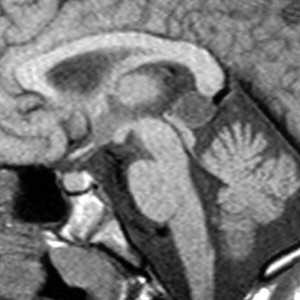

Киста кармана Ратке представляет собой редко встречающееся образование из остатков эмбриональной эктодермы (щель Ратке), расположенное между долями гипофиза. Выявляется в любом возрасте, но чаще в 50-60 лет. Клинические проявления связаны с масс-эффектом. При МРТ головного мозга выявляется небольшая (3-5мм) киста с четким контуром, без отека вокруг, однородная по структуре. Сигнал на МРТ головного мозга зависит от содержимого. При серозном содержимом сигнал типично жидкостный, при мукоидном киста светлая на Т1-взвешенных МРТ головного мозга. В 70-80% случаев внутри кисты выявляется неконирастирующийся узелок («пятно») - признак патогномоничный для кисты кармана Ратке. В редких случаях киста достигает больших размеров и даже выходит за пределы седла. Стенка кисты иногда усиливается при МРТ головного мозга с контрастированием. Дифференциальная диагностика при МРТ головного мозга должна проводиться с арахноидадьной и эпидермоидной кистами, тератомой, кистозной аденомой гипофиза и краниофарингиомой. Иногда при МРТ головного мозга киста кармана Ратке напоминает “пустое” турецкое седло. При маленьких размерах кисты ее на до дифференцировать на МРТ с микроаденомой гипофиза.

![Ratke cleft cyst]()

МРТ головного мозга. Т1-взвешенная сагиттальная МРТ. Киста кармана Ратке.